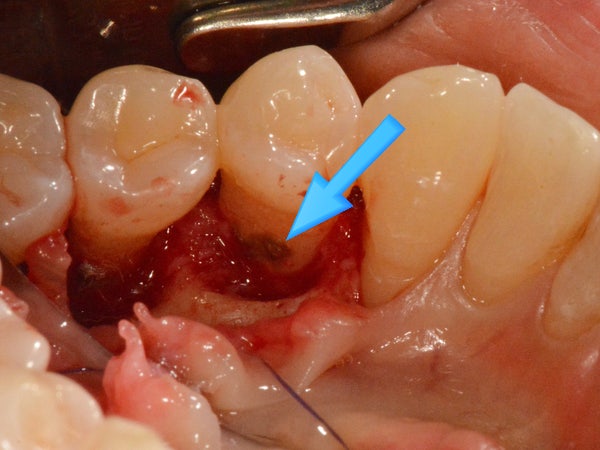

바람에도 이가 부딪히는 병이라 짠 이름이다. 잇몸이나 잇몸에 염증이 지속되는 질환으로 상태의 정도에 따라 #치은염 과 #치주염 으로 나눌 수 있습니다. ..우리의 입은 세균이 살기에 완벽한 환경입니다. 타액 때문에 촉촉하고 따뜻하며, 하루 3번 규칙적인 음식을 제공합니다 ㅎ 박테리아가 생존하기에 더 좋은 환경은 없습니다! 첫 번째 단계는 “건강 상태”입니다. 적절한 구강위생관리가 뒷받침되면 세균과 신체의 방어기제가 적절히 조화를 이루어 염증반응이 약해지지만 이 상태는 잇몸에 해를 끼치지 않는다. 이것은 가능하다. 2단계는 “치은염”으로 구강위생 관리가 제대로 이루어지지 않으면 치석이 치아 표면에 계속 존재하여 “치석”이 됩니다. 이 단계는 “잇몸 살”의 염증일 뿐이며, 스케일링으로 치석을 제거하면 약 2주 후에 건강한 잇몸이 회복됩니다. 그 다음은 “치주염, 치주염”의 단계입니다. 잇몸에서만 염증이 잇몸 뼈쪽으로 발전하기 시작합니다. 치석을 제거하지 않고 부적절한 구강 위생 관리가 지속되면 잇몸 질환이 빠르게 진행될 수 있습니다. 이렇게 치아 뿌리에 치석이 많이 붙어 있는 것을 볼 수 있습니다. 치석은 이렇게 치근 끝에 붙어 있는데, 그 주변의 잇몸뼈가 모두 녹아 없어진 것입니다. 이와 같이 치아를 지지하는 잇몸뼈가 완전히 녹아 치아가 뼈 위에 떠 있는 것을 볼 수 있어 치아를 지지하는 지지구조가 상실되어 필연적으로 치아가 흔들리게 되는데 이를 일명 풍치라고 합니다. 입안에 #플라크가 계속 쌓이다 -> 시간이 지나면 #치석이 된다 -> 치석 주위에 #잇몸염증이 생긴다 -> 염증반응이 진행되어 잇몸뼈가 녹는다. 위생관리와 #치석제거” 입니다. 치석제거의 깊이만 다를 뿐 치과치료의 대원칙은 “치석제거” 입니다. .하지만 이 복합치료의 명칭을 간단히 요약하자면. 잇몸에 붙어있는 치석을 제거하는 것입니다. 줌 보험은 매년 가입되기 때문에 #Zoom 을 경험해보지 않으신 분들은 많지 않을 것입니다. 나는 환자들에게 이것이 잇몸 치료의 “기본 치료”라고 말합니다. <第二步,根面平整+牙龈刮除术> 언급했듯이 치석 제거의 “깊이”에 따라 달라지는 이름일 뿐입니다. #발치 는 뿌리를 매끄럽게 만든다고 하여 발치+발치 라고도 합니다. #치은소파수술 은 염증 반응이 있는 병든 잇몸을 긁어내기 때문에 잇몸+소파라고도 합니다. 나는 환자들에게 잇몸 깊숙이 치석을 제거하는 것이 “마취 스케일링”이라고 말합니다. <第三步,牙龈切除术刮除法> 잇몸의 “비수술적” 치료였던 두 번째 단계는 이제 잇몸의 “외과적” 치료입니다. 이 수술을 받는 사람들의 많은 뼈가 어느 정도 녹았기 때문에 치아가 흔들리는 경우가 많아 ‘치아 뽑기 치료’ 또는 ‘치아 뽑기 수술’이라고 할 수 있습니다. 잇몸 치료에서 가장 중요한 것은 치석을 완전히 제거하고 건강한 박테리아 개체군이 다시 형성되어 뼈 재생이 일어날 수 있는 환경을 조성하는 것입니다. #치은박리술 은 치석이 너무 깊어 비수술적 방법으로 제거할 수 없을 때 잇몸을 절개하여 들어올리고 세척한 후 다시 봉합하는 치료법입니다. 여기서 정말 하고 싶은 말은 비수술적 치료 방법이 우선되어야 하지만 비수술적 치료가 우월하지 않다는 것입니다. 어느 정도 진행된 질병은 반드시 “수술”이 필요합니다. <第 4 步 – 牙槽骨再生> 치조골 재생 4단계는 치은절제술과 완전히 별개의 치료가 아닙니다. 치조골 재생에는 치은 절제를 위한 소파술이 항상 동반되기 때문입니다. 치조골이 재생되기 전에 치근 표면을 청소해야 합니다. 잇몸뼈가 녹은 부위에 뼈를 재생시키기 위해 “골형성유도제”를 첨가하거나 “골이식”을 시행합니다. 그러나 모든 잇몸뼈가 이식되고 무언가로 채워질 때 뼈가 되는 것은 아닙니다. 골이식은 골재생에 적합한 환경이 조성되었을 때 선택적으로 시행합니다. 치주질환, 즉 치주질환은 치료효과가 매우 강합니다. 특히 잇몸 긁기는 제가 정말 좋아하는 치료법입니다. 하지만 보험제도의 문제로 많은 치과의사들이 외면하는 경향이 있는 꼭 필요한 치료입니다. http://chika.tv/221921507429http://chika.tv/221921507429 각질제거의 강력한 효과는 이전 포스팅에서 확인하실 수 있습니다. 풍치로 고생하시는 분들! 흔들린다고 꼭 뽑아야 한다고 생각하지 마시고 치아 살릴 수 있는 마지막 기회를 놓치지 마시길 바라며 좋은 병원, 좋은 의사 만나시길 바랍니다 감사합니다. 이상호는 L2치과의원장이자 치주과의사인 최순호이다. 서울특별시 강남구 봉은사로 469 에스타워 4층 L2치과